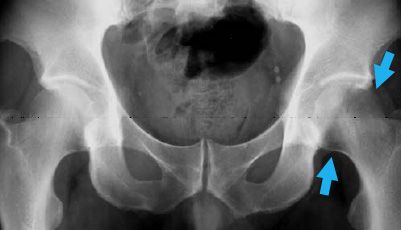

Pelvis x-ray

This X-ray of the pelvis shows early changes in bone density in the affected hip (arrows).

Reproduced from Korompilias AV, Karantanas AH, Lykissas MG, Beris AE: Transient osteoporosis. J Am Acad Orthop Surg 2008; 16:480-489.

• X-rays. In the early course of the disease (the first 6 weeks), X-ray images may show a slight decrease in the bone density of the femoral head, but this may be hard to see. Several months later, X-rays may show a dramatic loss of bone density with a near complete disappearance of the femoral head. This temporary loss of bone density is why the disease is termed "transient osteoporosis of the hip."